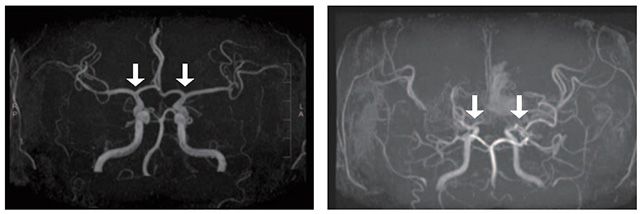

- ▲ 과관류증후군 발생 환자(G)와 그렇지 않은 환자(D)의 뇌혈류 속도 비교. 발살바호흡을 통해 동맥혈압이 낮아졌다가 정상으로 되돌아갈 때(Ⅳ구간), 과관류증후군 발생 환자는 그렇지 않은 환자보다 뇌혈류 속도가 서서히 증가하고, 뇌혈관 반응성이 떨어지는 것으로 나타났다. /이미지 제공=서울대병원

연구팀은 성인 모야모야병 환자 24명의 수술 전후 동맥혈압과 뇌 혈류 속도를 경두개 초음파검사로 측정해 뇌 자동조절 기능을 평가하는 ‘VM_OI 지수(발살바 과반응 지수)’를 개발했다. 이후 수술 전후 환자의 뇌 혈류 반응성을 정밀 분석해 VM_OI 지수를 확인했다.

그 결과, 과관류증후군 발생 환자는 그렇지 않은 환자보다 VM_OI 지수가 낮아 혈압 변화에 대한 뇌 혈류 반응성이 떨어지는 것으로 나타났다. 수술 후 시간이 지나면서 이 지수는 점차 회복돼 과관류증후군이 일시적이고 회복할 수 있는 특성을 가진다는 점도 확인됐다. 이번 연구 결과는 국제 학술지 ‘Scientific Reports’에 게재됐다.